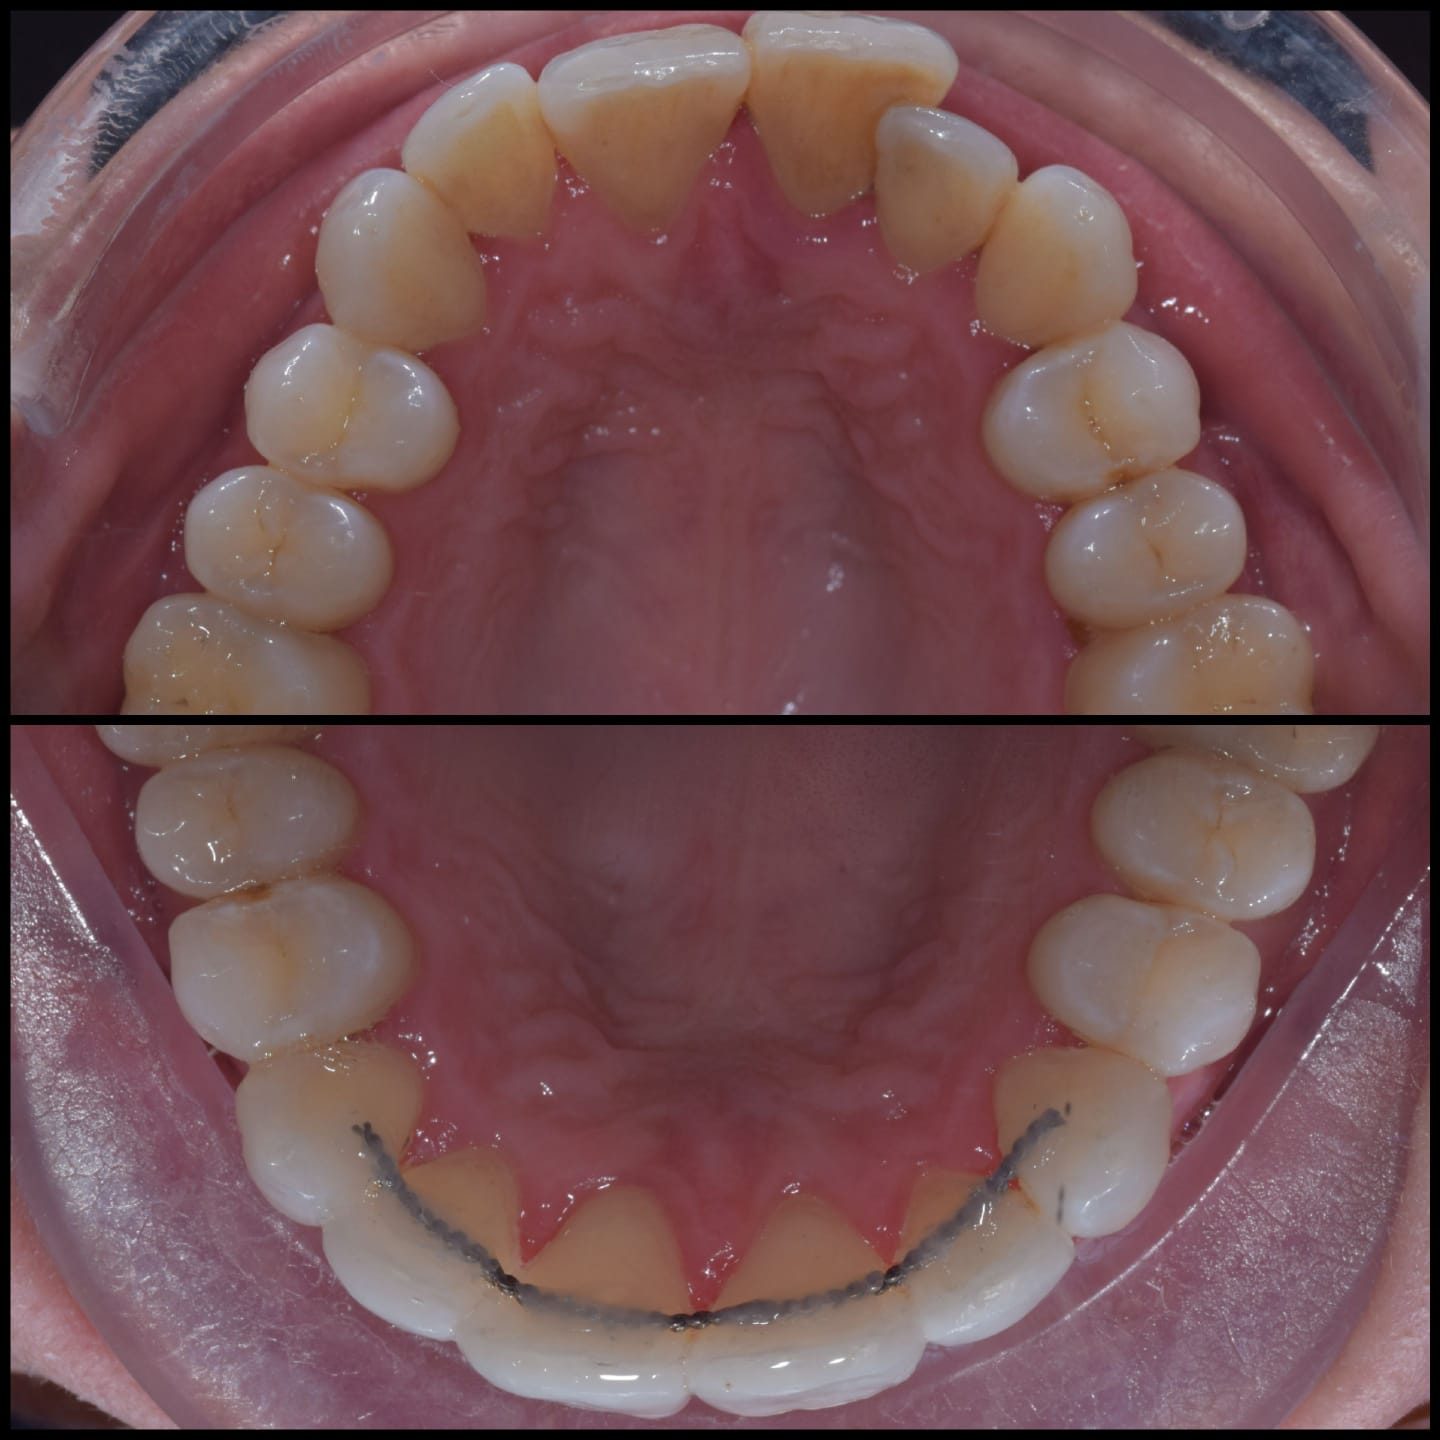

Invisalign is a clear alternative to traditional metal braces, offering a discreet and convenient way to achieve a straighter smile. Unlike traditional braces, Invisalign aligners are removable and nearly invisible, allowing you to eat, drink, and live your life without restriction. With Invisalign, you can straighten your teeth without the hassle and self-consciousness of metal braces.

Invisalign is a well-known system for straightening teeth in the most discreet way. It works by using a series of clear aligners that fit comfortably over the teeth to gently move them into the desired position over time. There are no fixed brackets or wires used, in fact, the aligners are completely removable.